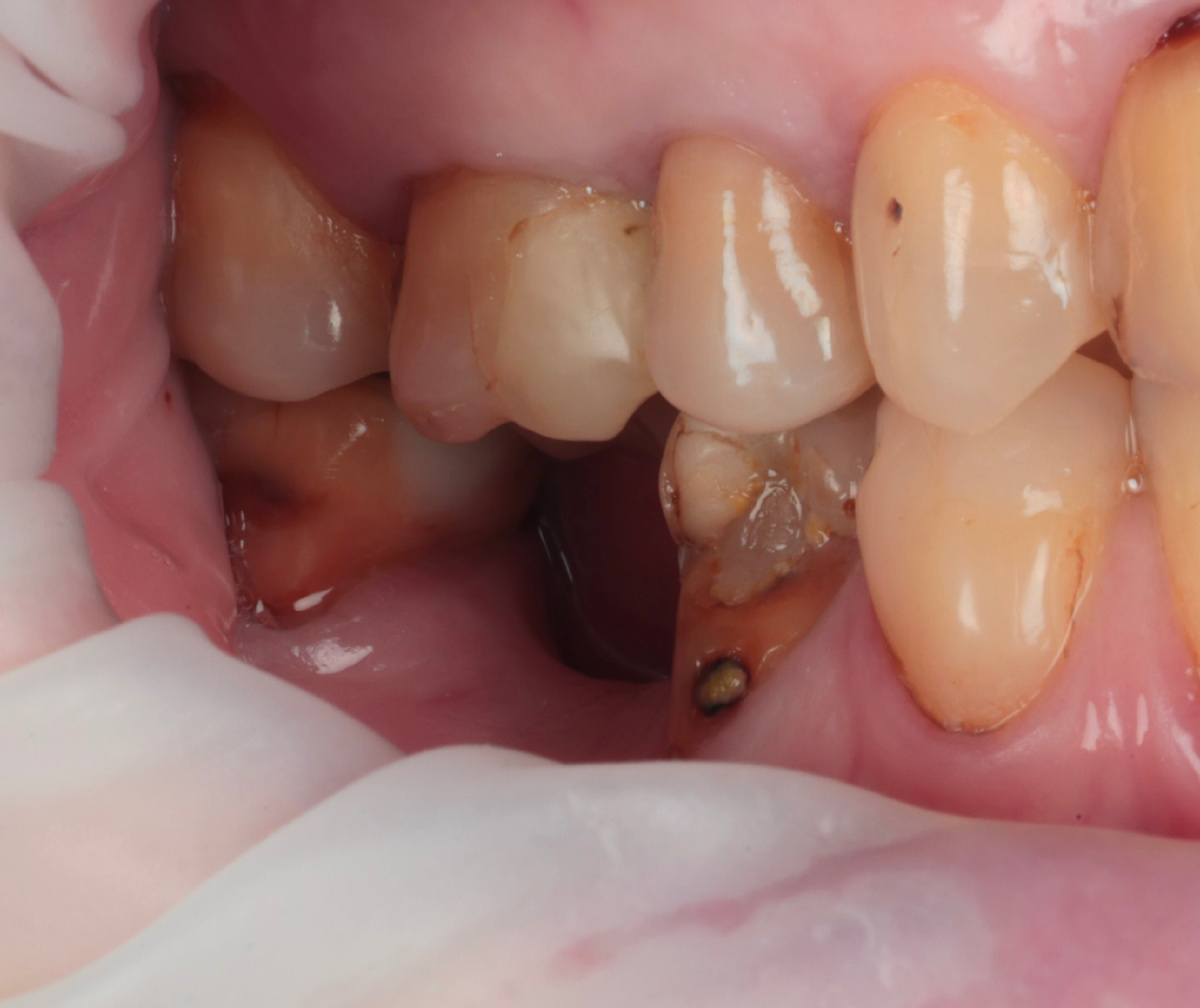

Раз каналы запломбированы адекватно и изменений на верхушках нет, перелечивать их не нужно. Терапевт выполняет подготовку под коронки - убирает старые пломбы и дефектные ткани. Вот что осталось после того, как убрали часть дефектных тканей:

Можно увидеть, что от зубов остались рожки да ножки после обработки. На такое коронки не установить - не за что цепляться.

Врач выполняет билдапы - культевые надстройки:

С обязательным укреплением качественными стекловолоконными штифтами. Мы используем Macrolock - дорого, но оно того стоит. Надёжная адгезия, предсказуемый результат.

И вот, новые красивые культи готовы ко встрече с ортопедом.